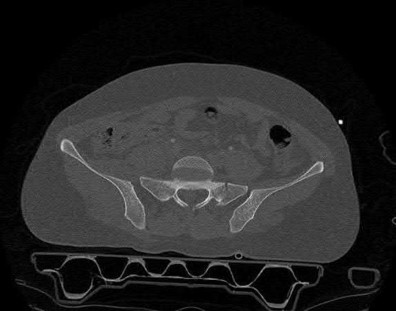

A 23-year-old female is an unrestrained driver in a motor vehicle collision, sustaining the injury shown in Figure A. She subsequently undergoes reduction and percutaneous bilateral iliosacral screw placement. Which of the following is the most likely neurologic complication associated with percutaneous iliosacral screw insertion?

Figure A shows an unstable bilateral pelvic ring injury. Percutaneous posterior iliosacral screw fixation places the L5 nerve root at risk as it courses across the sacral ala. Injury to the L5 nerve root would typically result in weakness in great toe extension and sensory changes on the dorsum of the foot. It is important to notice that L5 often partially innervates tibialis anterior along with L4, so weakness to ankle dorsiflexion may be present as well. Illustration A shows the post-operative films with bilateral iliosacral screws.

Routt et al examined the sacral slope and sacral alar anatomy in cadavers and a series of consecutive patients. They determined that the pelvic outlet and lateral sacral plain films provide the best plain radiographic views of the sacral ala. They recommended routine usage of these views intraoperatively to guide screw placement.

In another study, Routt et al reported on the early complications of percutaneous placement of iliosacral screws for treatment of posterior pelvic ring disruptions. While technically challenging, this technique leads to less blood loss and lower rates of infection compared to traditional open techniques.

Illustration B displays the root diagrams for sensation, reflex, and motor of the L4-S1 nerves.